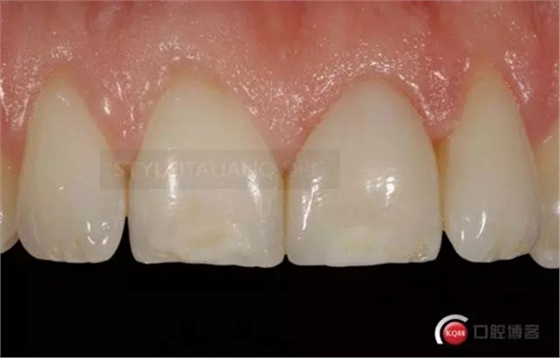

Until the immediate final outcome

Control one month check shows a natural smile

And the vestibular

and palatal tissue healing